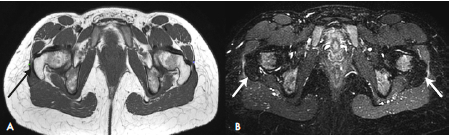

Magnetic resonance and ultrasound (cross-sectional plane) of the right hip of an asymptomatic patient, where the relationship between the iliotibial band, the tendon of the gluteus maximus and the greater trochanter is evident.

Figure 1: Magnetic resonance and ultrasound (cross-sectional plane) of the right hip of an asymptomatic patient, where the relationship between the iliotibial band, the tendon of the gluteus maximus and the greater trochanter is evident.

Source: Document obtained during the study.